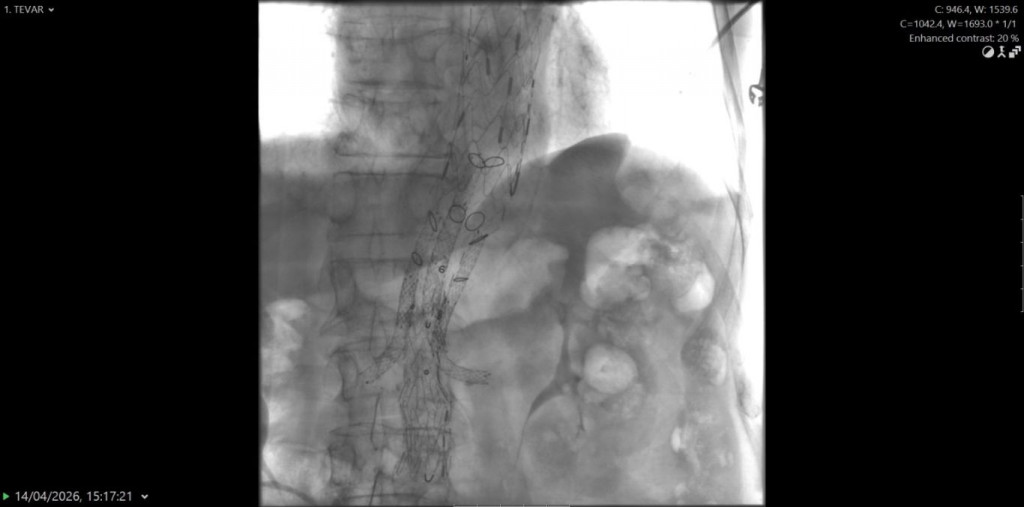

Riječ je o proceduri poznatoj kao BEVAR (branched endovascular aortic repair), koja je primijenjena kod pacijenta s istodobnom aneurizmom i disekcijom torakalne aorte, životno ugrožavajućim stanjima koja zahtijevaju visoko specijaliziran pristup.

Zahvat je izveden 14. travnja, a proveli su ga specijalisti radiologije uz sudjelovanje kardiovaskularnih kirurga, uz stručnu podršku kolega iz KBC Osijek.

"Ovakvi zahvati predstavljaju vrhunac suvremene endovaskularne medicine i zahtijevaju iznimnu koordinaciju multidisciplinarnog tima koji uključuje interventne radiologe, kardiokirurge, vaskularne kirurge, anesteziologe, inženjere radiologije, instrumentarke i anestezičare. Tijekom zahvata ugrađena su ukupno tri stenta duž aorte, od arterije subklavije do bifurkacije aorte. Kako bi se osigurala adekvatna prokrvljenost vitalnih organa, postavljen je posebno dizajniran stent s otvorima za bubrežne arterije te arterije koje opskrbljuju crijeva", rekao je Bogdan.